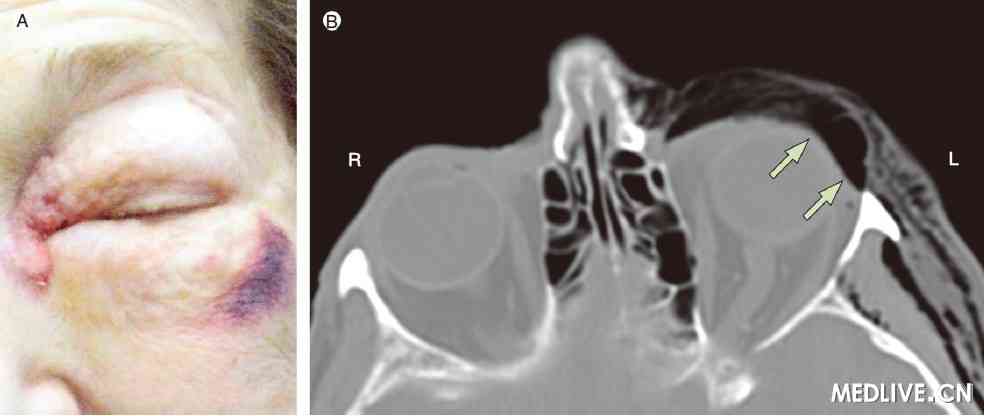

2009年2月, 一84岁的女性因左臂骨折到我处就诊。采用夹板保守治疗。其同时伴有左侧上颌肿胀和淤斑。面部X线片检查未见骨折。出院时,患者于打喷嚏后立即出现左眼失明。左眼眶区严重肿胀(附图A)并有捻发音。眼眶CT显示眼眶气肿,但无明显骨折(附图B)。眼科及耳鼻喉科检查显示眼及鼻咽功能正常。应用去氧肾上腺素喷鼻及抗生素治疗。建议患者不要擤鼻子。

A. 左眼眶区大范围碰伤及肿胀。B. CT显示气体进入左眼眶区,但无开放性骨折

眼眶气肿比较少见,由气体进入眼眶部组织所致。可以发生于鼻窦感染、颌面部创伤或手术的患者[1]。眼眶壁的极薄区(筛骨眶板),是最常见的骨缺损部位,能够使空气通过内侧的鼻旁窦到达眼眶。此患者在随后的眼科检查中表现出正常的眼球运动和视力。其外侧上颌淤斑,CT显示无骨折。眼眶壁可能已经出现未被发现的解剖学缺损,打喷嚏致其开裂从而使空气流向眼眶组织。出院10 d后,随访观察发现气肿完全消退。